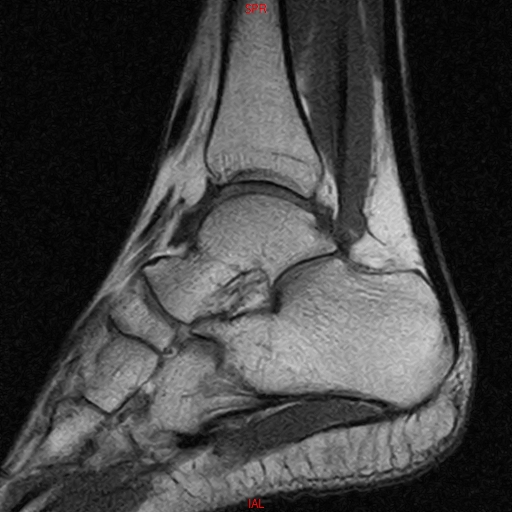

• Resonancia NORMAL TOBILLO SAGITAL T1

• Resonancia NORMAL PIE SAG T1